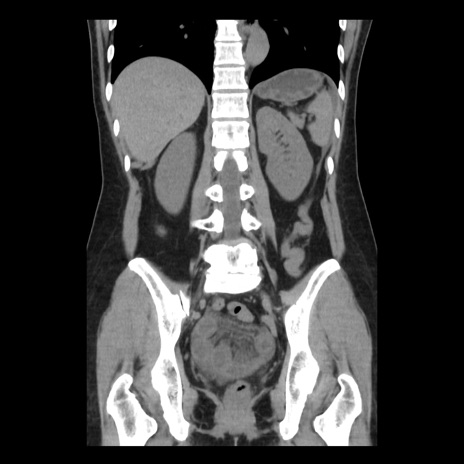

症例10(冠状断像)

【症例】 50歳代女性

【主訴】 腹痛

【現病歴】前日生レバーを食べた。今朝に排便あり。 昼前に突然発症の腹痛を生じ、当院救急外来を受診した。

【既往歴】 子宮筋腫にてで子宮全摘後

【身体所見】 意識清明、腹部:平坦、軟、下腹部やや左を中心に圧痛・反跳痛あり、筋性防御あり

【データ】WBC 7800、CRP 0.07